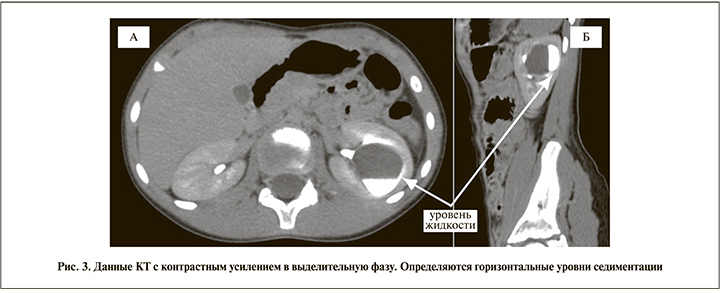

На серии КТ почек и мочевыводящих путей, выполненных с внутривенным мультифазным контрастным усилением (нативная, артериальная, нефрографическая, выделительная фазы): почки обычно расположены, нормальных размеров и формы. Паренхима правой почки не изменена. Отмечается кистоподобное образование в паренхиме левой почки, в центральных ее отделах, с четкими округлыми контурами, без явной капсулы. Содержимое его однородное, плотностью в нативной фазе около 16 HU. Размерами: сагиттально до 35 мм, поперечно до 28 мм, вертикально до 34 мм. Образование расположено парапельвикально, истончает паренхиму на уровне своего расположения и, вероятно, имеет связь с полостью ЧЛС. В выделительной фазе исследования контраст появляется в полости образования, расположен с расслоением и образованием горизонтального уровня седиментации (рис. 3). Наличие уровня последней считаем одним из патогномоничных признаков дивертикула. По результатам КТ и отсроченных рентгеновских снимков визуализировалось резкое расширение средней группы чашечек (дивертикулоподобное), оттесняющее верхнюю и нижние группы. Микционная цистография пузырно-мочеточниковый рефлюкс не выявила.